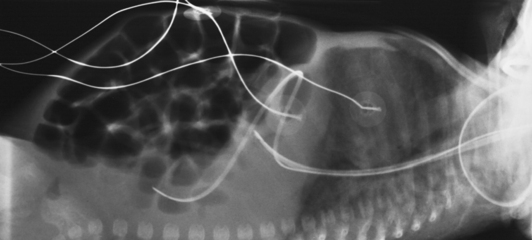

Fig. 28-11 Mobile AP chest radiographs in critically ill patients. A, Patient with postoperative left thoracotomy and chest tube, infiltrate or atelectasis in the left base, segmental elevation of the right hemidiaphragm, and soft tissue emphysema on the left. B, Patient with small left pleural effusion and moderate right effusion, cardiomegaly, mild pulmonary vascular congestion, and calcification and torsion of the aorta.